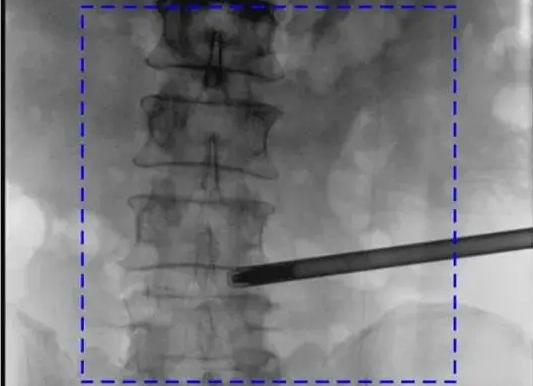

齐齐哈尔市中医医院从十年前引进第一台影增小C到后来的平板小C、移动式平板介入中C,再到近期刚刚完成装机,投入使用的平板三维C形臂,均选择了同一品牌PERLOVE。下面来回顾下齐齐哈尔市中医医院C型臂更新换代之路:...

高压发生器的功率参数很大程度上决定了C形臂的成像效果,现如今,具备大功率高压发生器的C形臂普遍受到医院采购方的青睐,比如普爱医疗PLX C7600系列三维平板C形臂。...